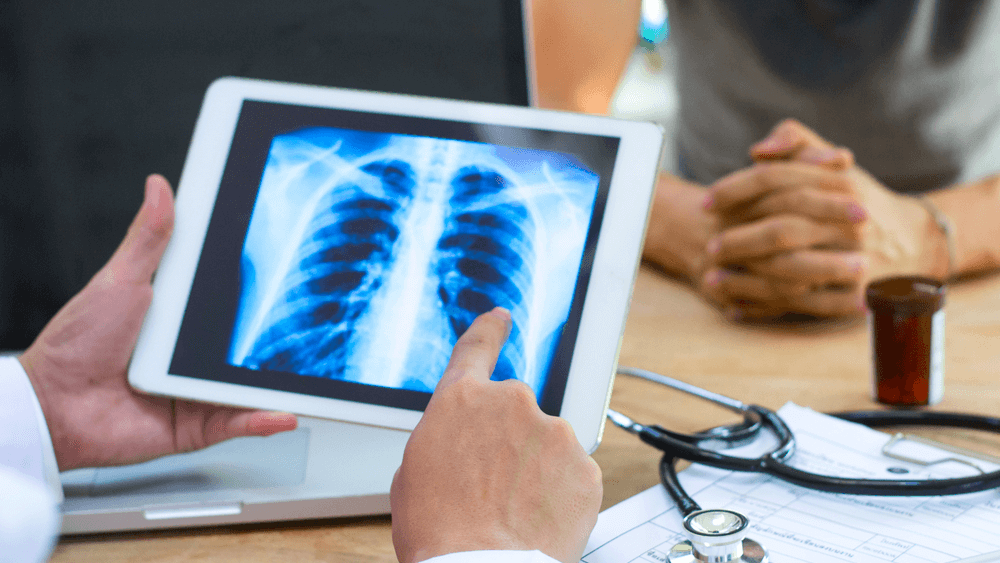

Digital X-ray